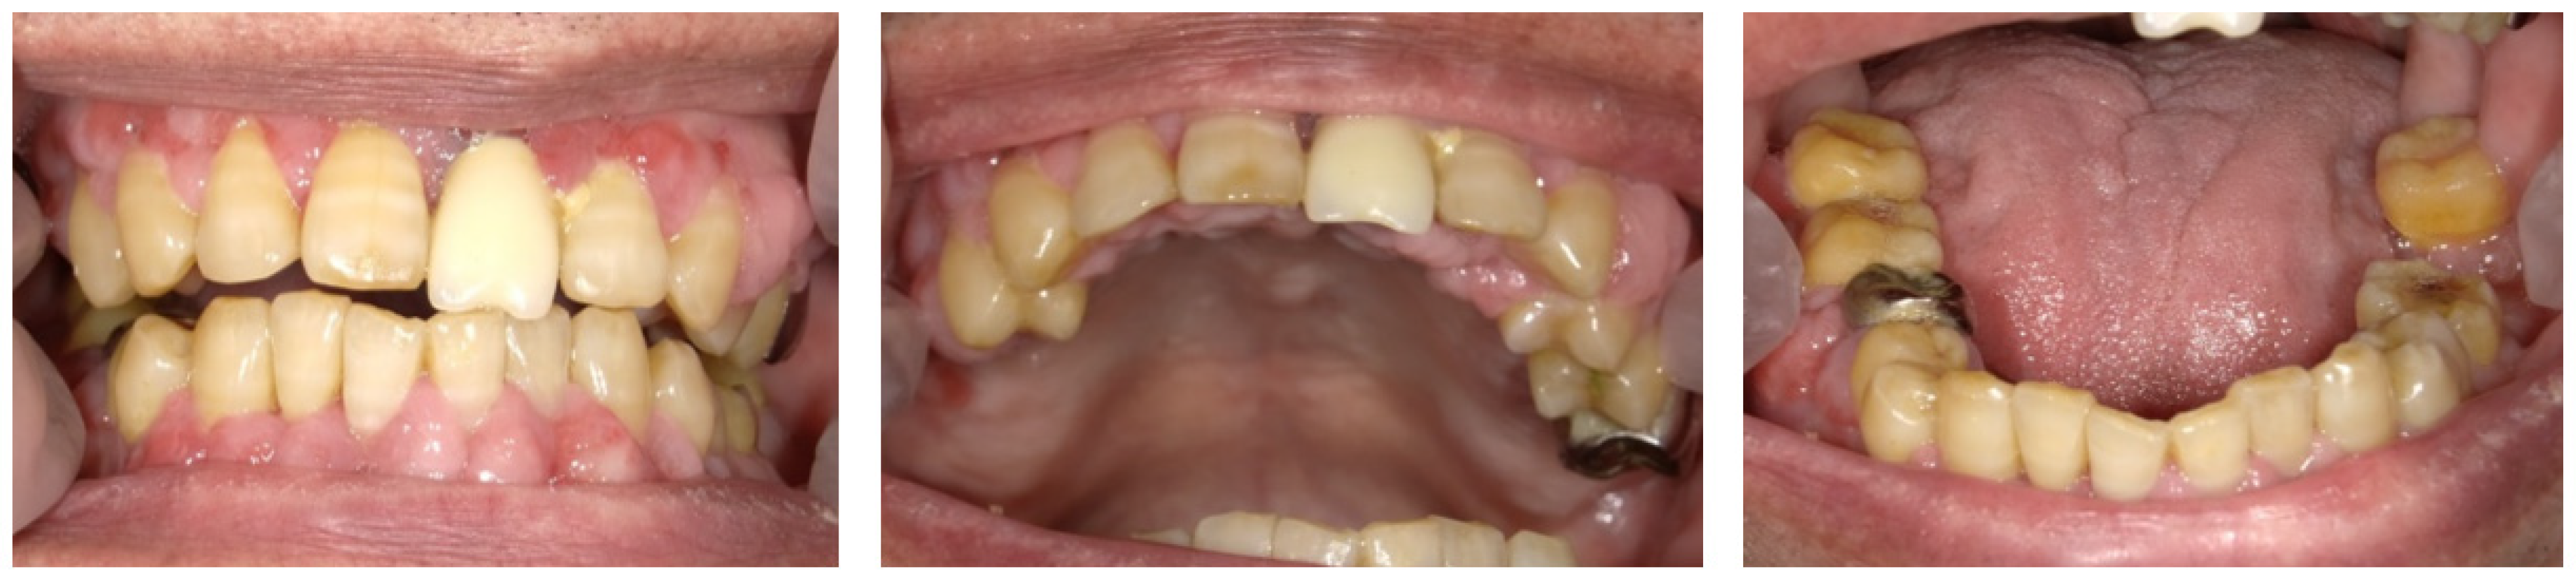

2.1. Day 1: First Examination